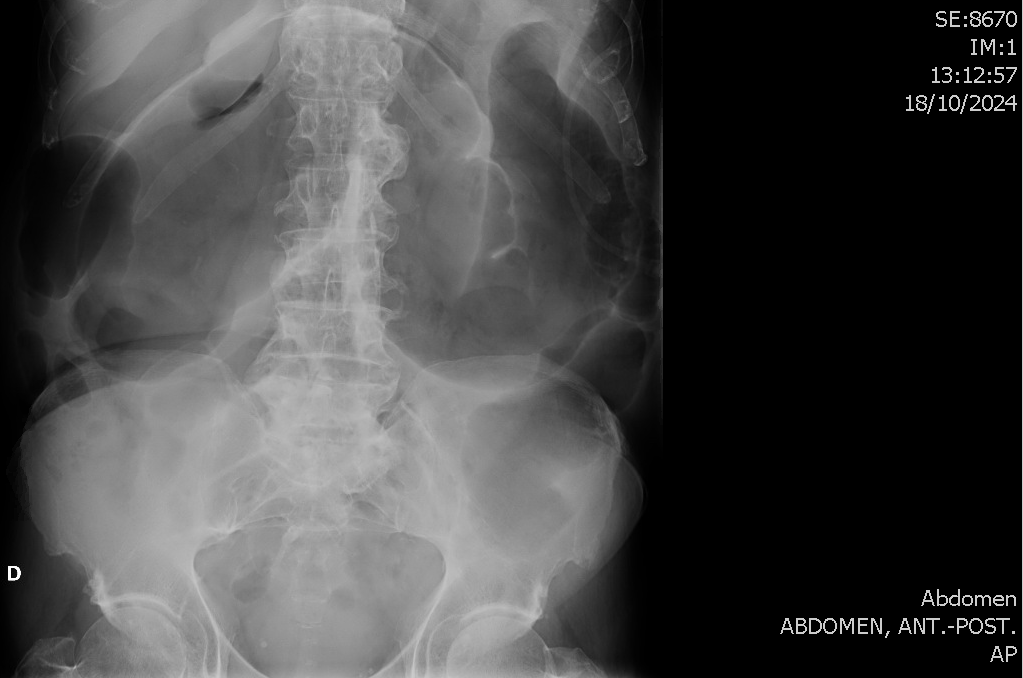

Analíticas, radiografías abdominales y TC abdominal a nivel hospitalario.

Ante los hallazgos ecográficos derivo a Urgencias Hospitalarias, donde se objetiva un Fracaso Renal Agudo que condiciona el ingreso del paciente. Rx abdominal en bipedestación anodina. Durante el ingreso presenta empeoramiento progresivo de la distensión abdominal objetivable en radiografías seriadas y descartándose obstrucción mediante TC abdominal. Es diagnosticado de megacolon tóxico secundario a infección por Campylobacter jejuni.

Evolución favorable. Persiste leve dilatación sigmoidea en rx realizada 1 mes tras el alta.